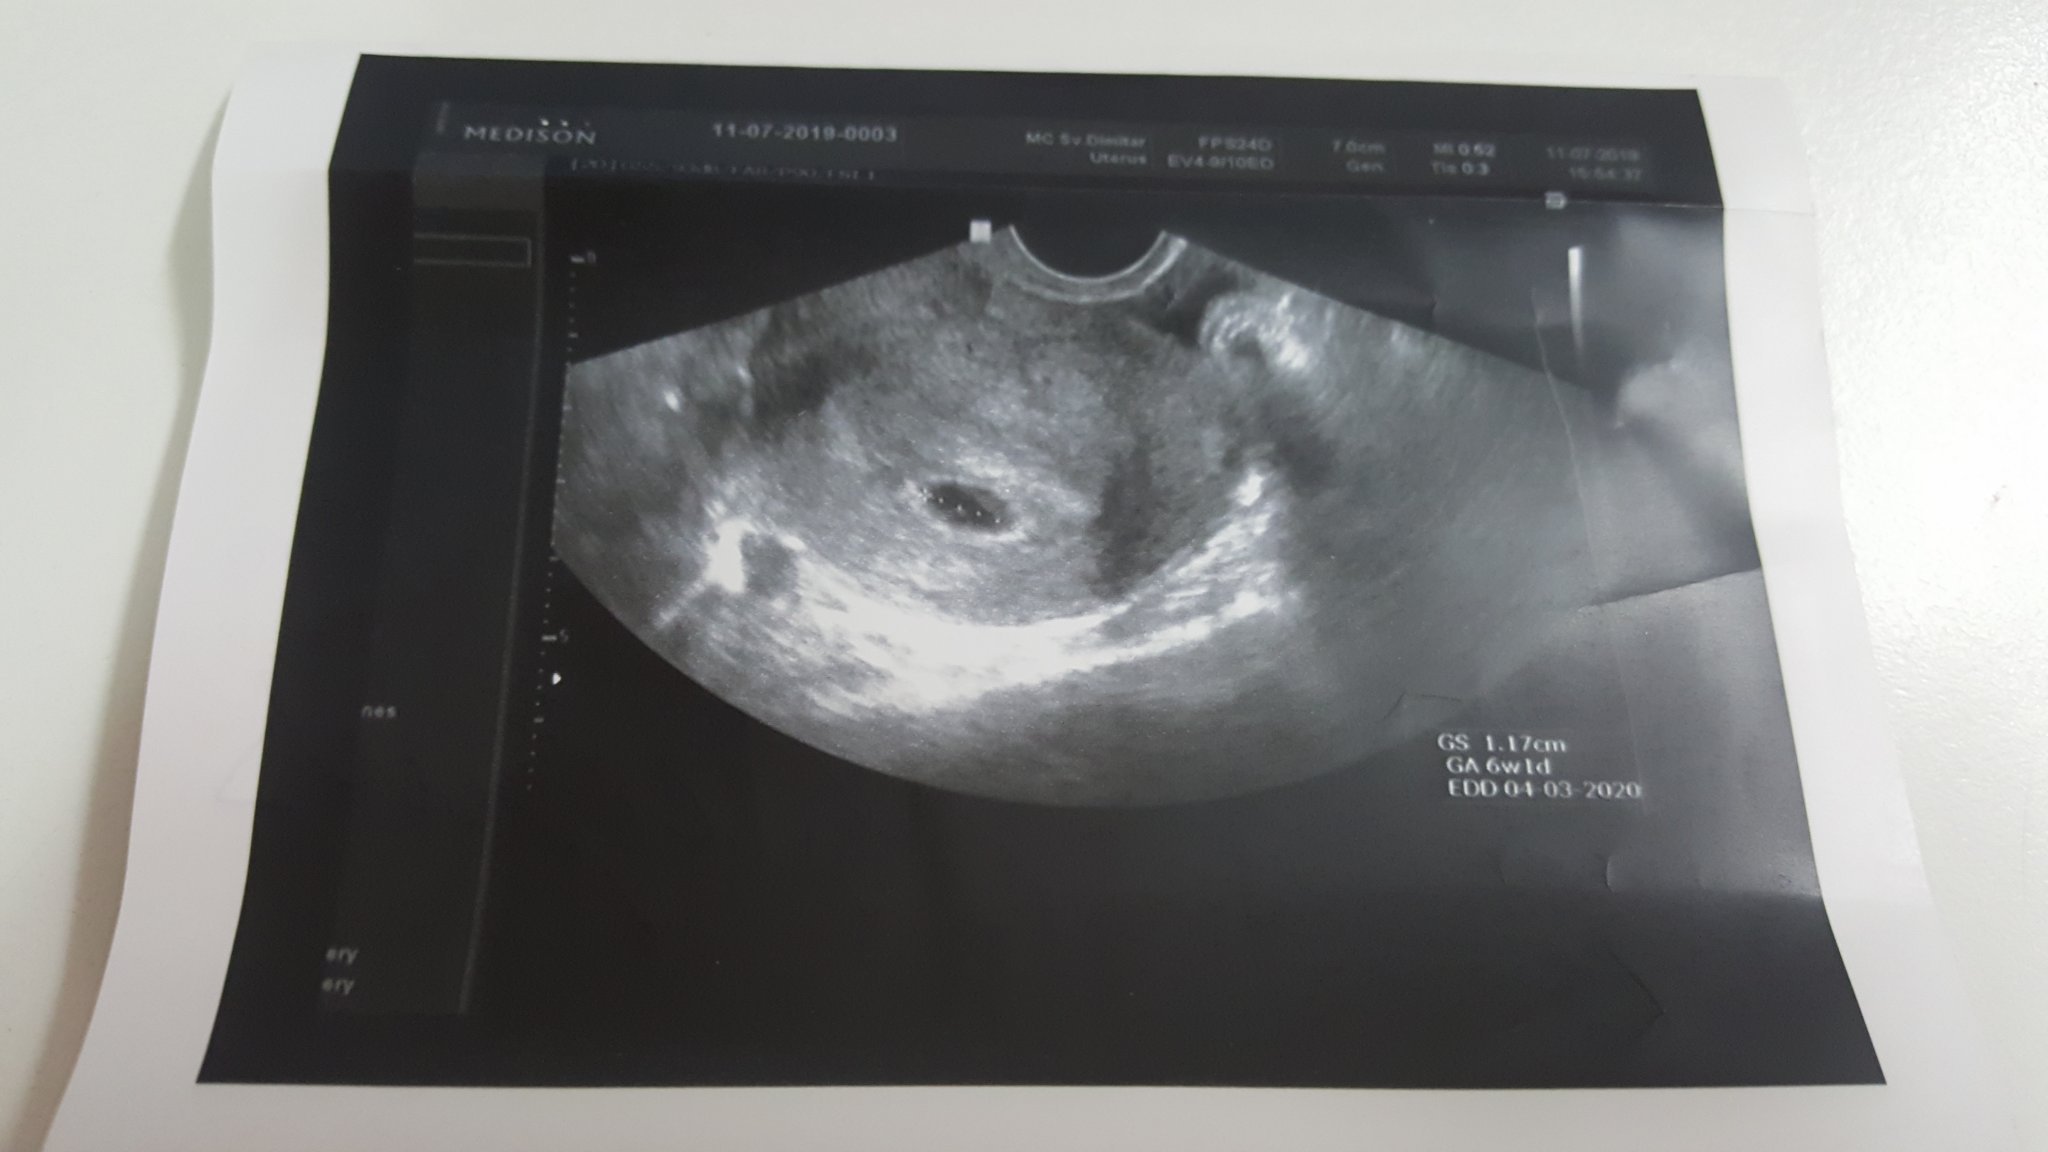

Здравейте момичета!Казвам се Катрин на 28г.от гр.София,приятно ми е 🙈🙃.Това ми е втора бременност.За съжаление миналата година на 21.05.почина 6год.ми дъщеричка Габи...Надявам се с бременноста ми всичко да е наред.Последният ми цикъл беше на 04.06.2019,на 05.07.-видях двете чертички и отидох на гинеколог.След това,онзи ден,на 11ти бях отново и докторът каза,че вероятния ми термин ще е на 10.03.2020г.И ми каза нещо за седмиците,което не разбрах и ще ви помоля да ми обясните:Значи по нз си кое съм била 5г.и3д.,а на ехографа пише 6w1d и,че още е рано за сърдечна дейност и ми записа час за 19ти.Качвам снимката и ако някой е по-усведомен от мен,моля да ми каже в коя седмица съм.Предварително благодаря! 😘

За седмиците знам от първата ми бременност, че ти си 5г.с. и 3 дни, но размерите на бебето отговарят като за по голямо бебе, което е 6седмици и 1ден. Това не е опасно, добре е. Може да си имала ранна овулация, но и да не си имала пак е нормално. 9 тия месец дори стомахчето на  моето дете вървеше с 2 седмици назад и пак се оказа, че вс. е ок и нямаме проблеми... С две думи-не се претеснявай!!!